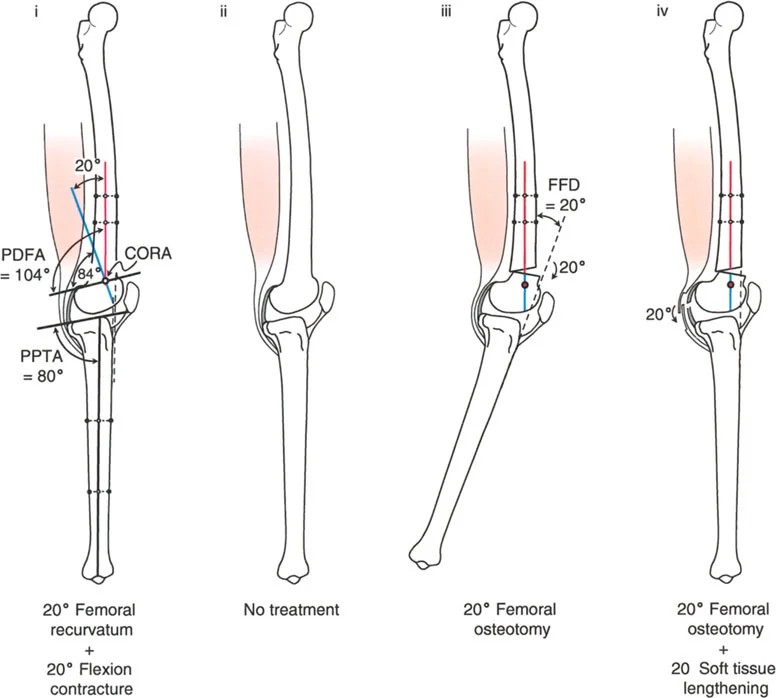

- على الرغم من أن الركبة الارتدادية هي فرط تمدد، إلا أنه في بعض الحالات، يمكن أن يترافق التشوه العظمي بتقلص في الأنسجة الرخوة يحد من انثناء الركبة. هذا التقلص يمكن أن "يخفي" أو "يعوض" جزئيًا فرط التمدد العظمي، مما يجعل الركبة تبدو في وضع تمدد طبيعي ظاهريًا.

- على سبيل المثال، إذا كان هناك ارتداد فخذي بمقدار 20 درجة مع تقلص انثناء 20 درجة، فقد تبدو الركبة في وضع تمدد كامل (0 درجة) ولكنها تعاني من فقدان في مدى الانثناء.

* قد لا يكون هناك فرط تمدد سريري واضح (HE = 0°)، لأن تقلص الانثناء يعوض التشوه العظمي.

* ومع ذلك، سيظل المريض يعاني من فقدان في مدى انثناء الركبة.

* في هذه الحالات، قد تكون الركبة "مستقرة" نسبيًا ولا تسبب أعراضًا شديدة إذا كانت غير مؤلمة.

- زاوية الانحناء البعيدة للفخذ (PDFA - Posterior Distal Femoral Angle): تقيس زاوية الجزء السفلي من عظم الفخذ. القيمة الطبيعية حوالي 84 درجة. الزيادة في هذه الزاوية (أكثر من 84 درجة) تشير إلى ارتداد فخذي.

- زاوية الانحناء القريبة للظنبوب (PPTA - Proximal Posterior Tibial Angle): تقيس زاوية الجزء العلوي من عظم الساق. القيمة الطبيعية حوالي 80 درجة. الزيادة في هذه الزاوية (أكثر من 80 درجة) تشير إلى ارتداد ظنبوبي.

- مركز دوران الزاوية (CORA - Center of Rotation of Angulation): يتم تحديد هذا النقطة على الأشعة السينية لتحديد مكان التشوه العظمي بدقة، وهو أمر بالغ الأهمية لتخطيط عملية قطع العظم.

- الركبة الارتدادية بسبب الارتداد الفخذي مع تقلص انثناء:

- إذا كان هناك ارتداد فخذي (PDFA > 84°) ولكن لا يوجد فرط تمدد سريري (HE = 0°)، فهذا يشير إلى وجود تقلص انثناء مصاحب يعوض التشوه العظمي.

- إذا كان فرط التمدد (HE) أقل من درجة الارتداد الفخذي، فهذا يعني وجود تقلص انثناء جزئي.

أ. قطع العظم الفخذي لتصحيح الارتداد الفخذي:

- متى يتم إجراؤها: عندما يكون التشوه الرئيسي في عظم الفخذ البعيد.

- الإجراء: يتم إجراء قطع للعظم (عادة قطع عظم انثناء) في الجزء البعيد من عظم الفخذ، عند مركز دوران الزاوية (CORA)، لإعادة محاذاة العظم.

- الهدف: تصحيح فرط تمدد الركبة واستعادة المحاذاة الطبيعية.

- مثال: لتصحيح ارتداد فخذي بمقدار 20 درجة، يتم إجراء قطع عظم انثناء فخذي بمقدار 20 درجة.